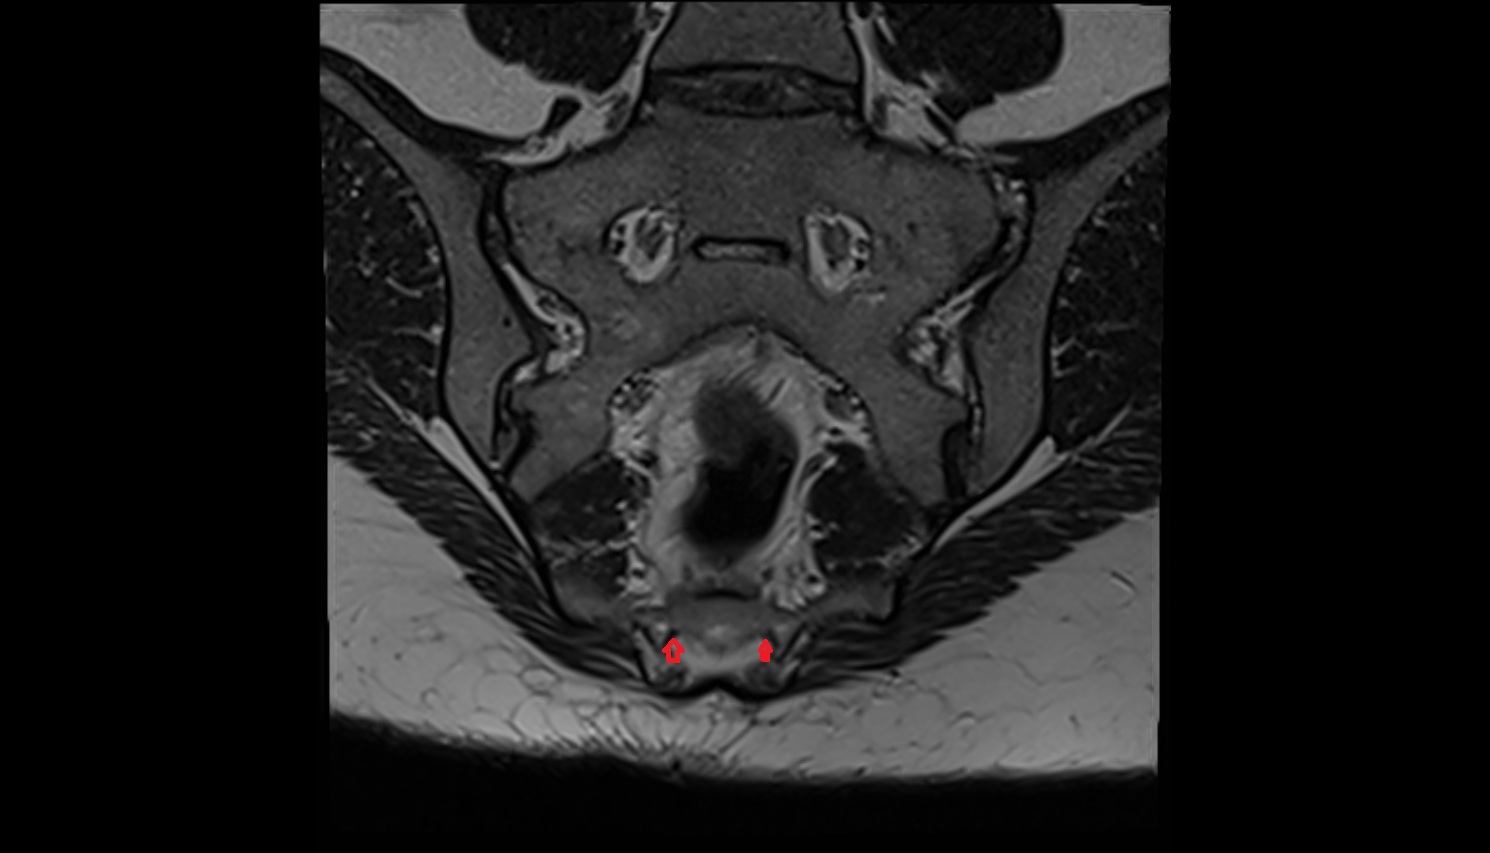

- Uterus

- Cervix of uterus

- Vagina

- Ovaries

- Right ovary

- Left ovary